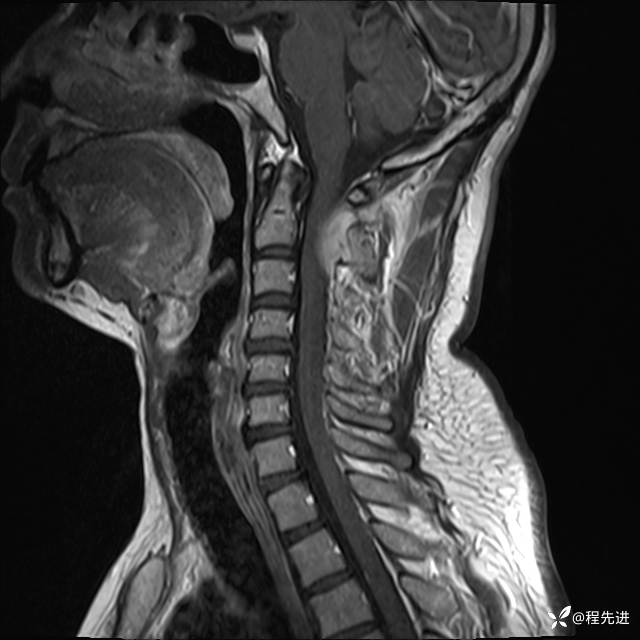

MRI平扫+增强:

T1: